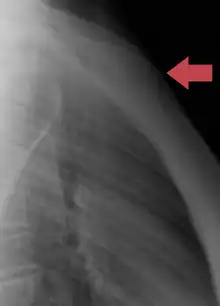

Fractures

Fractures of the sternum are rather uncommon. They may result from trauma, such as when a driver's chest is forced into the steering column of a car in a car accident. A fracture of the sternum is usually a comminuted fracture. The most common site of sternal fractures is at the sternal angle. Some studies reveal that repeated punches or continual beatings, sometimes called "breastbone punches", to the sternum area have also caused fractured sternums. Those are known to have occurred in contact sports such as hockey and football. Sternal fractures are frequently associated with underlying injuries such as pulmonary contusions, or bruised lung tissue.[12]